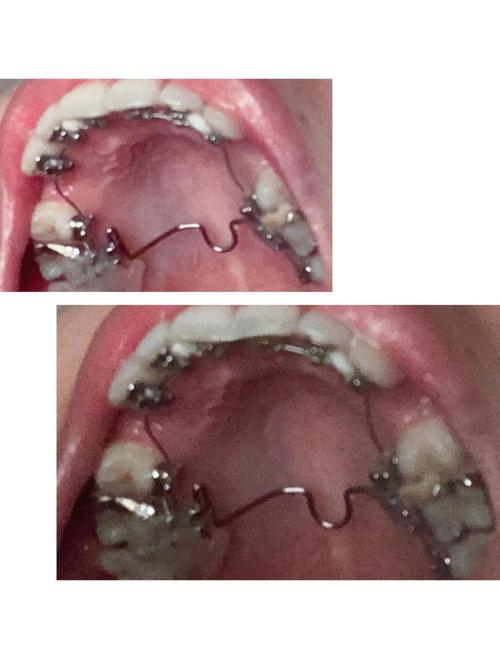

术前正畸阶段(6-12个月)

目的是排齐牙列、消除牙代偿(如“龅牙”患者的前牙过度唇倾),通过戴固定矫治器(金属托槽、陶瓷托槽或隐形牙套)调整牙齿位置,为手术创造骨移动空间,此阶段需每月复诊,由正畸医生监控牙齿移动情况。 -

(图片来源网络,侵删)- 术前准备:拍摄头颅侧位片、CBCT(三维重建)、取模型,进行头影测量分析,模拟手术效果;